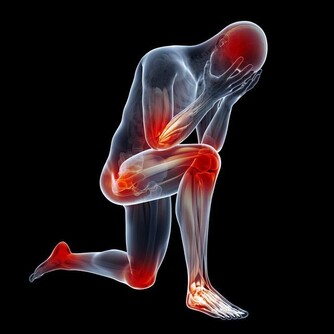

2. 骨盆疼痛

伴隨著不正常的出血,你還可能出現盆腔疼痛。疼痛可能是瀰漫性的,也可能是劇烈的疼痛或鈍痛,可以出現在骨盆的任何部位。如果近期出現新的骨盆疼痛,或與月經週期無關,最好看醫生。另外,性交或排尿期間疼痛也是警告信號。